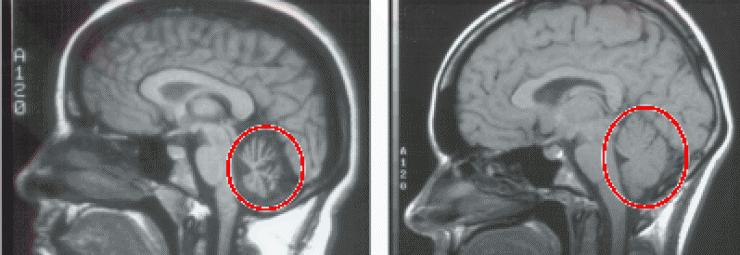

肝腹水是肝硬化的并发症,肝硬化患者要提前预防,肝腹水对于人体肝脏损伤非常严重,你了解肝腹水吗,肝腹水的这些症状看你有吗?赶快来自侧一下。腹部饱满及移动性浊音肝腹水可使腹部饱满,叩诊可闻移动性浊音,此为典型的肝硬化腹水...